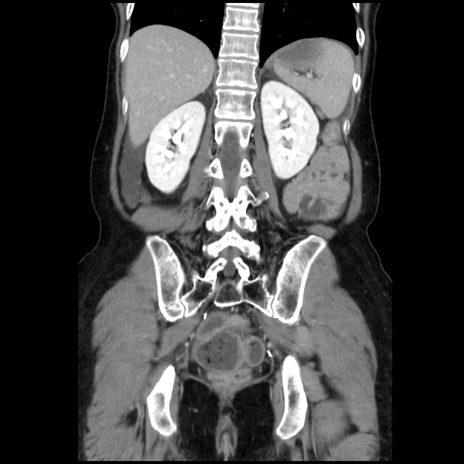

症例32(冠状断像)

【症例】40歳代 女性

【主訴】上腹部痛、嘔気・嘔吐

【現病歴】約9時間前頃から急に上腹部痛、嘔気、嘔吐が出現。改善しないため救急要請。

【既往歴】子宮頚癌(広汎子宮全摘術、放射線療法)、腸閉塞

【身体所見】腹部:平坦、軟、腸雑音亢進、上腹部を中心に腹部全体に圧痛あり。

【データ】WBC 8400、CRP 0.03